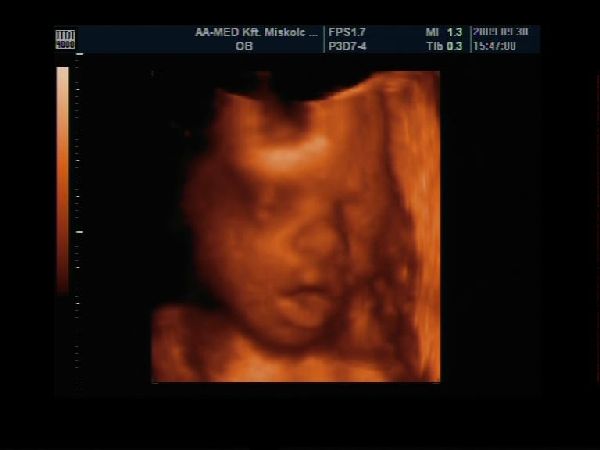

Van egy pár percem a gép előtt, gyorsan teszek fel Nektek képecskéket :wink:

Szerintem olyan szép pofija van és természetesen nekem Ő a legszebb :lol: :lol: :lol:

Szerencsére szépen mutatta magát, láttuk mindenét, most már biztos, hogy cunis :lol:

Apa is nagyon élvezte, főleg, hogy ennyire jól lehetett látni a kis tündérkénket :D

A képek 27 hetese és 1 napos: Kép Kép Kép Kép

Akella, ez egy gyönyörűség, ahogy mosolyog, meg cuclizza az ujjacskáját, olyan cuki :D . Istenem, de rég volt, hogy ilyen képeket nézegettünk UH-on. :|

De azt nem bírom kihagyni,hogy Akella kis gyönyörűségét meg ne dícsérjem!!!Csodaszép az a kis mosoly!!(kissé irigy vagyok :wink: ...na de ami késik...)